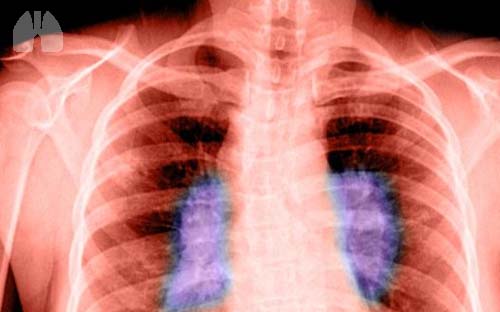

Although not specifically named in the CDC report, the list of underlying conditions accurately describe many patients with sarcoidosis, a systemic granulomatous disease that frequently affects the lung. It should not be surprising, in this pandemic, that these patients, and their physicians, are anxiously wondering whether they are more susceptible to COVID-19 or whether they might have a more severe clinical course. Thus, the report from Rossides et al. in the current issue of the European Respiratory Journal, is timely. While not explicitly answering the question of susceptibility of sarcoidosis patients to COVID-19 infection, the paper addresses this important concern in general and highlights an under-researched area in sarcoidosis literature: risk of secondary infections.

In their analysis, Rossides et al. examined hospitalisations and outpatient visits recorded in the Swedish National Patient Register to determine risk of serious hospitalised infections (SI), defined as a hospitalisation with an infectious disease as the primary discharge code (ICD-9). Over 8700 newly diagnosed sarcoidosis cases identified from 2003–2013 were matched to 86 000 general population controls on age, sex and residential location. Information on initial immunosuppressive therapy was available for 77% of the study population. They found that rates of SI and recurrent SI were 1.8-fold and 2.8-fold higher, respectively, in patients with sarcoidosis compared to the general population.

The current paper by Rossides et al. re-emphasises this latter observation; the negative impact of therapy. Immunosuppressive therapy is recommended, according to Wells's Law, for impaired quality of life or fear of danger (i.e. threatened organ failure). Corticosteroids are considered first line of treatment due to their ability to rapidly suppress granulomatous inflammation. Patients can relapse upon withdrawal, thus these agents are often prescribed for prolonged periods resulting in side-effects that can significantly impact quality of life. In the current analysis, risk of first SI was three-fold higher among those treated with immunosuppressants compared to those who were not. Although the indications for therapy, the length of therapy, and the cumulative dose of immunosuppressants used in the sarcoidosis cohort are unknown, prescribed treatment alone at the start of diagnosis was sufficient to increase one's risk for infection.